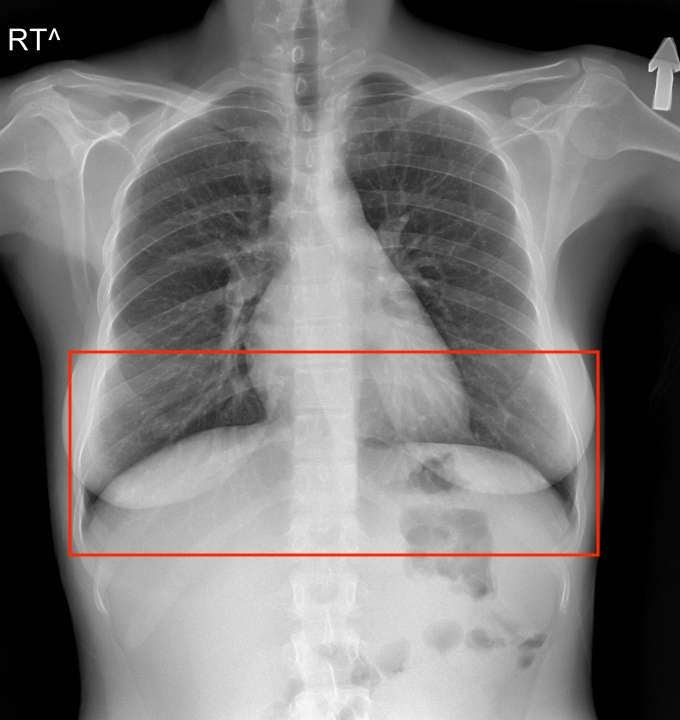

医学成像包含透明胶片

我们所说的“医学成像包含透明胶片”的意思是必须区别对待遮挡物

一个在另一个前面的对象可能会出现在另一个后面。众所周知,由于缺乏注意力,AI 对遮挡的处理很差,而透明物体可能会更糟。

不过幸运的是,对于人工智能来说,看起来透明的器官、细胞或骨骼比一块玻璃要明显得多。

看看下面的胸部 X 光片,自己决定——肺是在横膈膜后面还是前面?

胸部 X 光片显示肺的下部,在横膈膜前面向后延伸,在横膈膜后面向前延伸

答案是……两者都有!传统的计算机视觉方法无法感知肺部被遮挡的部分;然而,深度神经网络可以很容易地学会发现它。